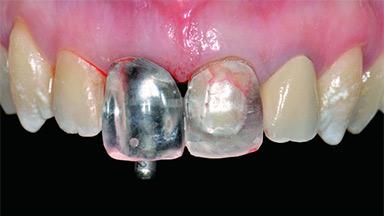

A 30-year-old patient presented at our clinic with a chief complaint of pain in her endodontically treated right maxillary central incisor (tooth 11) with a post-and-core and a fixed single crown. She had a very high lip line, a medium to thin soft-tissue phenotype, and a medium scalloped gingival contour. She also had high esthetic expectations because of her young age and beautiful smile. However, her expectations were realistic and she understood the risks of the treatment. At the initial clinical examination there was a slight mobility of tooth 11; no fistula was observed. The patient also had a single crown on the adjacent tooth 21. Both restorations were old and esthetically deficient. A digital periapical radiograph showed a very small periapical radiolucency, a thick intraradicular post, and no separation between root fragments.

Prosthesis Type FDP

Provisional Implant-Supported Prosthesis Prosthodontic margin > 3 mm apical to mucosal margin Prosthodontic margin > 3 mm apical to mucosal margin